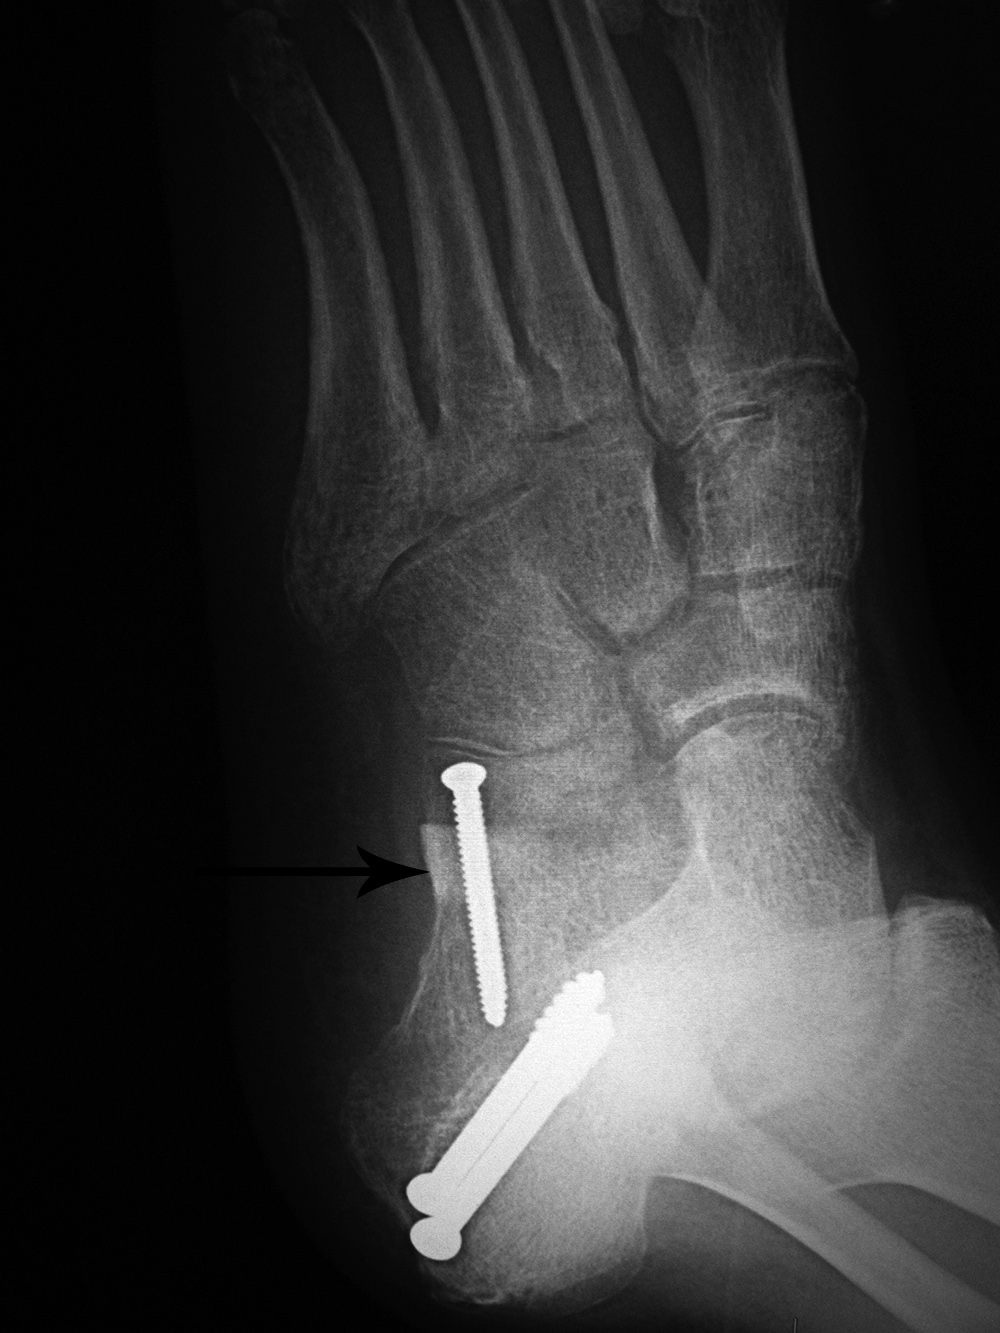

Calcaneal autogenous bone graft

46 year-old man with posterior tibial tendon tear, Achilles tendon contracture, and planovalgus foot alignment. He was treated with Achilles tendon reattachment and two large partially threaded cancellous bone screws stabilizing a mid-calcaneal osteotomy. In the anterior portion of the calcaneus there is an autogenous iliac crest bone plug (arrow) stabilized by a fully threaded cortical bone screw.